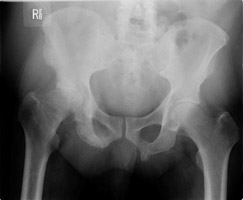

- Click on the image for a larger versionAScanogram. This patient with renal cell carcinoma shows a comminuted fracture of the proximal right femoral shaft.